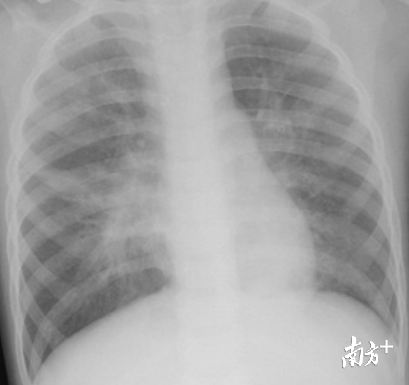

入院时孩子在呼吸机辅助通气下仍喘憋、呼吸困难,气管导管内吸出粘稠浓痰,血气提示二氧化碳潴留,给予加强雾化、翻身、拍背、吸痰处理,效果不理想,孩子呼吸机参数进行性增高,二氧化碳潴留进行性加重(>100mmHg),双肺呼吸音明显减低,潮气量低,呼吸机送不进气,呼吸困难不能缓解。

镜子下可见小豪右肺右上叶、中叶、下叶各段支气管管腔内多量黄白色胶冻物堵塞,左肺左主支气管已被胶冻物完全堵塞气道。

许医师耐心、细致的进行反复灌洗、吸引,毛刷、钳夹等多种技术手段相结合,一条条树枝状的内生异物被逐一从右肺吸出,左肺主支气管仍堵塞,支气管镜不能通过。时间在不知不觉中流逝,窗外天色已深,孩子一侧肺部通畅,呼吸机参数有所下降,二氧化碳潴留有所改善。

孩子左肺仍堵塞不通,值班的医护继续呼吸机通气,间歇以少量生理盐水行气道冲洗,胸部电动按摩振荡拍背、结合体位引流吸痰等。12小时后行第2次电子支气管镜,许医师娴熟的将4.0mm和2.8mm镜交替使用,瞄准堵塞物采用大负压吸引,结合毛刷、钳夹等,钳夹时轻轻将钳深入约1cm左右,力量太大易将异物夹断,太小易使异物滑脱,如同绣花,更象踩钢丝,一点一点解除堵塞。约2小时后,左肺气道慢慢通畅了,呼吸机参数下降了,二氧化碳分压正常了,孩子呼吸平顺了。